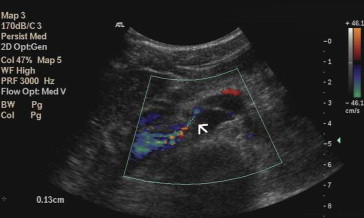

Renal Doppler ultrasound was performed, and peak velocity (PV) was measured at the hilar and aortomesenteric portions of the LRV. In the upright position, the PV in the hilar and aortomesenteric portion of the LRV were 28.4 and 200 cm/s, respectively, and the PV ratio was 7.04; the anteroposterior diameters were 11.1 mm and 1.3 mm (Fig. 1), respectively, and the ratio of the AP diameters was 8.6. The pressure gradient between LRV and inferior vena cava was 16 mmHg. It also showed dilatation of the right renal pelvis. Magnetic resonance angiography (MRA) showed that the LRV is compressed between the AO and the SMA, and the hilar portion of the LRV was distended (Fig. 2). The SMA delineated sharply from the AO, and the aortomesenteric angle where the LRV crosses was 15°. Retrograde pyelograthy (Fig. 3) and magnetic resonance urography revealed right-sided ureteropelvic junction stenosis and hydronephrosis. From these findings, a diagnosis of left nutcracker syndrome and right UPJO was made.

Magnetic resonance angiography showing a compressed left renal vein between the ...

Magnetic resonance angiography showing a compressed left renal vein between the abdominal aorta and the superior mesenteric artery. Left renal vein with distended hilar portion (arrow).